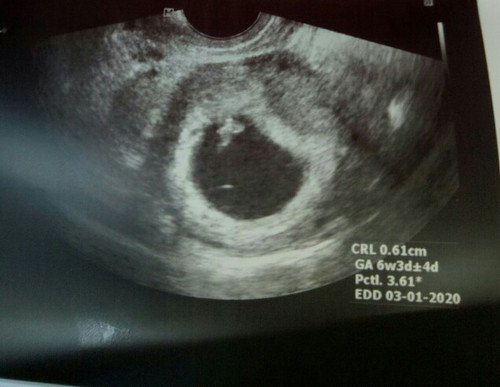

Maganda po ba yung position??

Pakitingnan naman po if maganda po posisyon nya. FTM here po.